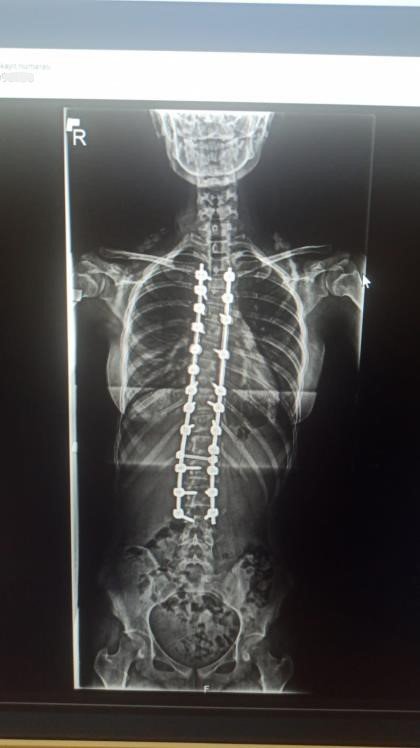

Skolyoz Hastası Zeynep Füzyon Cerrahisi İle Sağlığına Kavuştu

ANTALYA (İHA) – Samsun'da 4 yıldır skolyoz hastası olan 10'uncu sınıf öğrencisi Zeynep Pehlivan'ın sırtında ve belinde bulunan eğrilikler Antalya'da özel bir hastanede gerçekleştirilen füzyon cerrahi tedavisi ile düzeltildi. Ameliyattan bir gün sonra yürümeye başlayan ve 4'üncü günde taburcu edilen Zeynep Pehlivan, "Sağlığıma tekrar kavuştuğum için çok mutluyum" dedi.

Samsun'da yaşayan ve bir süredir skolyoz hastası olan 10'uncu sınıf öğrencisi Zeynep Pehlivan, tedavi için Antalya Memorial Hastanesi Ortopedi ve Travmatoloji Bölümünden Doç. Dr. Ömer Bozduman'a ulaştı. Yapılan görüşmelerin ardından Pehlivan ve ailesi Antalya'ya davet edildi. 4 gün önce Antalya'ya gelen Zeynep Pehlivan için ameliyat kararı alındı. Ameliyatla genç kızın sırtında ve belinde bulunan eğrilikler enstrümantasyonlu bir sistemle füzyon cerrahi tedavisi yaparak düzeltildi. Ameliyatın hemen ardından bir gün sonra yürümeye başlayan Pehlivan, 4 gün sonra taburcu edildi.

Zeynep'in skolyoz hastalığından dolayı uzun zamandır takiplerinde olduğunu belirten Doç. Dr. Ömer Bozduman, "Rahatsızlığı gerilemek yerine ilerleme olunca müdahale etmeye karar verdik. Ameliyatını gerçekleştirdik. Sırtında ve belinde olan eğriliklerini enstrümantasyonlu bir sistemle füzyon cerrahi tedavisi yaparak düzelttik. Ameliyattan sonra birinci gün yürüttük. Problem yaşamadık, dördüncü gün taburcu edeceğiz. Zeynep'in en sık hareketlenmelerinin olduğu boyun sırt bileşkesine beliyle kalça bileşkesine dokunmadık. Daha az hareketsiz olan sırt bölgesine füzyon cerrahi yaptık. Bundan sonra çok fazla bir fonksiyon kaybı olacağını düşünmüyoruz" dedi.